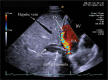

Introduction: Optimal positioning of double lumen bicaval canula for extracorporeal membrane oxygenation (ECMO) support used as a rescue measure in refractory hypoxaemia is essential to facilitate adequate oxygenation, prevent recirculation and avoid complications. Method: Echocardiography via transoesophageal or transthoracic windows can be used as guidance and as a surveillance technique to prevent cannula malposition. We describe a case of Double-Lumen Bicaval VV ECMO cannula malposition leading to a massive retrograde hepatic venous flow. Conclusion: Rapid echocardiographic diagnosis was pivotal in preventing potentially fatal complications.